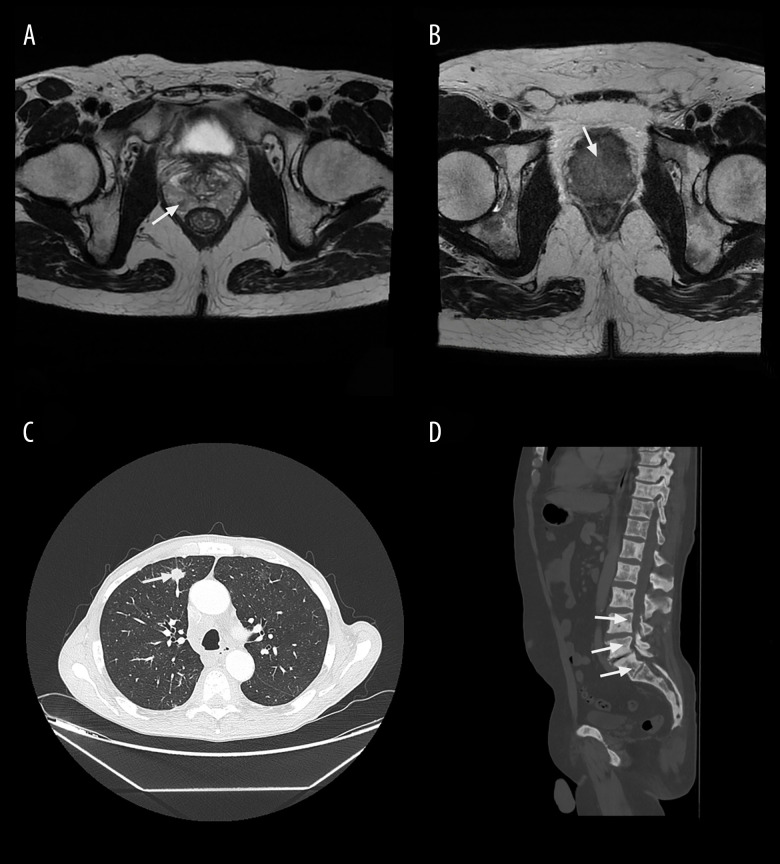

背景前列腺癌的发生和发展是一个多步骤的过程,涉及多种生长因子、激素和细胞因子。本研究旨在测量前列腺腺癌患者血清中不同细胞因子的浓度,并确定它们与前列腺特异性抗原(PSA)水平和疾病分级的相关性。材料与方法 这项横断面研究于 2023 年 3 月至 2024 年 3 月在波斯尼亚和黑塞哥维那莫斯塔尔大学医院中心肿瘤诊所进行。共纳入 50 名前列腺腺癌男性患者,其中 28 人未经证实有转移(PC 组),22 人有转移性疾病(MPC 组)。使用化学发光微粒子免疫测定法测定血清中总 PSA(tPSA)、游离 PSA(fPSA)和复合物 PSA(cPSA)的浓度,使用流式细胞计数珠检测法测量血清中细胞因子的浓度。结果 MPC 组的血清 tPSA、fPSA 和 cPSA 水平均高于 PC 组。PC 组血清中单核细胞趋化蛋白(MCP)-1 水平明显高于 MPC 组(P=0.008)。在 PC 组中,白细胞介素(IL)-10 的血清水平与 cPSA 显著相关。在 MPC 组中,血清中 IL-1ß、肿瘤坏死因子 (TNF)-α 和 IL-23 的浓度与疾病分级明显相关。结论 我们的研究强调了 MCP-1 在前列腺癌发病中的重要性,而 IL-10 是唯一血清水平与 cPSA 显著相关的细胞因子。IL-1ß、TNF-α和IL-23的血清浓度可作为疾病分级的潜在生物标志物。

BACKGROUND The development and progression of prostate cancer are multistep processes involving several growth factors, hormones, and cytokines. This study aimed to measure the serum concentrations of different cytokines and determine their correlation with prostate-specific antigen (PSA) levels and disease grade in patients with prostate adenocarcinoma. MATERIAL AND METHODS This cross-sectional study was conducted from March 2023 to March 2024 at the Clinic of Oncology of the University Hospital Center in Mostar, Bosnia and Herzegovina. Altogether, 50 male patients with prostate adenocarcinoma were included, of whom 28 had no proven metastases (PC group) and 22 had metastatic disease (MPC group). Serum concentrations of total (tPSA), free (fPSA), and complexed (cPSA) PSA were determined using a chemiluminescent microparticle immunoassay, whereas serum concentrations of cytokines were measured using a flow cytometry bead-based assay. RESULTS The MPC group had higher serum tPSA, fPSA, and cPSA levels than the PC group. The PC group had significantly higher serum levels of monocyte chemotactic protein (MCP)-1 than the MPC group (P=0.008). In the PC group, serum levels of interleukin (IL)-10 significantly correlated with cPSA. In the MPC group, serum concentrations of IL-1ß, tumor necrosis factor (TNF)-alpha, and IL-23 significantly correlated with disease grade. CONCLUSIONS Our study emphasizes the importance of MCP-1 in the development of prostate cancer, while IL-10 was the only cytokine whose serum level significantly correlated with cPSA. Serum concentrations of IL-1ß, TNF-alpha, and IL-23 may serve as potential biomarkers for disease grade.